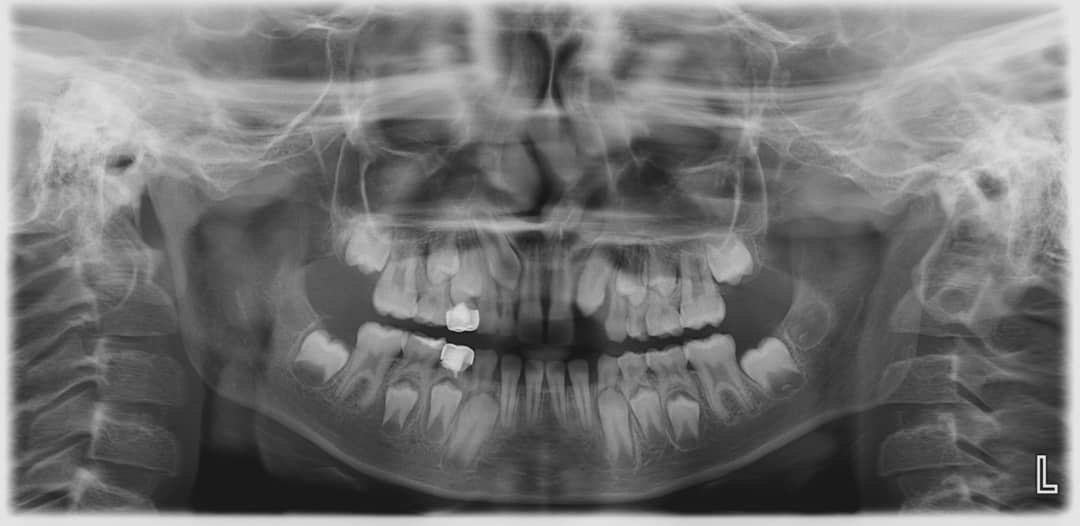

3. How old is the patient with the following X ray?